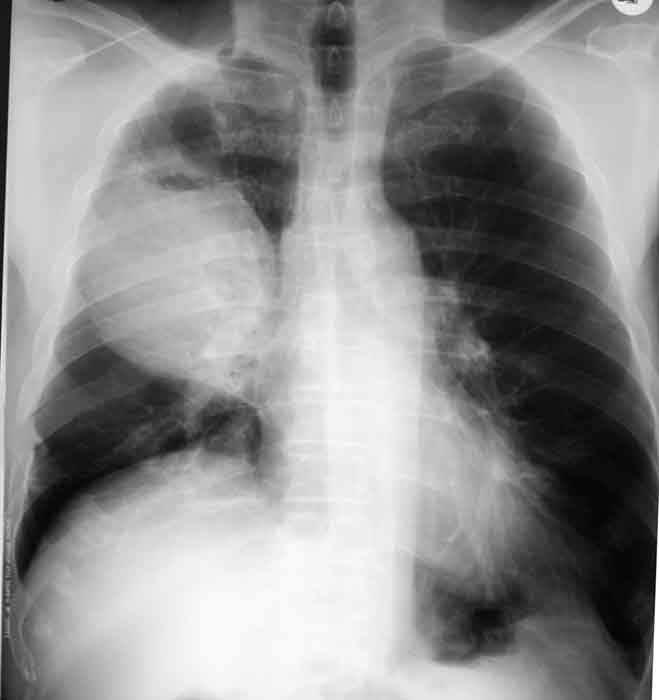

What is the pathology shown in this image?

bronchogenic carcinoma

What is the classification of this pathology?

neoplastic and malignant